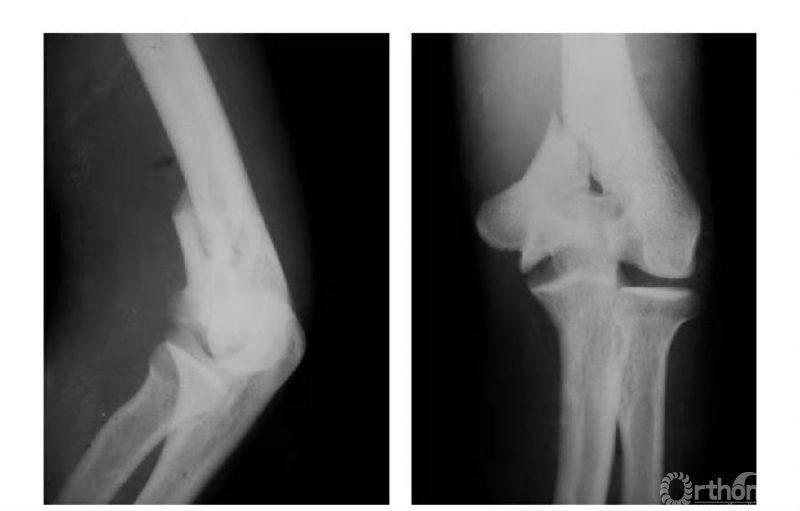

例3:肱骨内髁长斜形劈裂骨折(折线长约10cm)(图3)。

图3

例1:肱骨内髁滑车关节面骨折,骨块陷入鹰嘴窝内,致肘内翻畸形(图4)。

图4